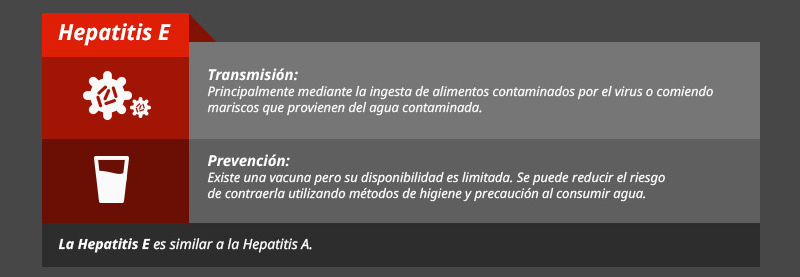

Tipos de hepatitis